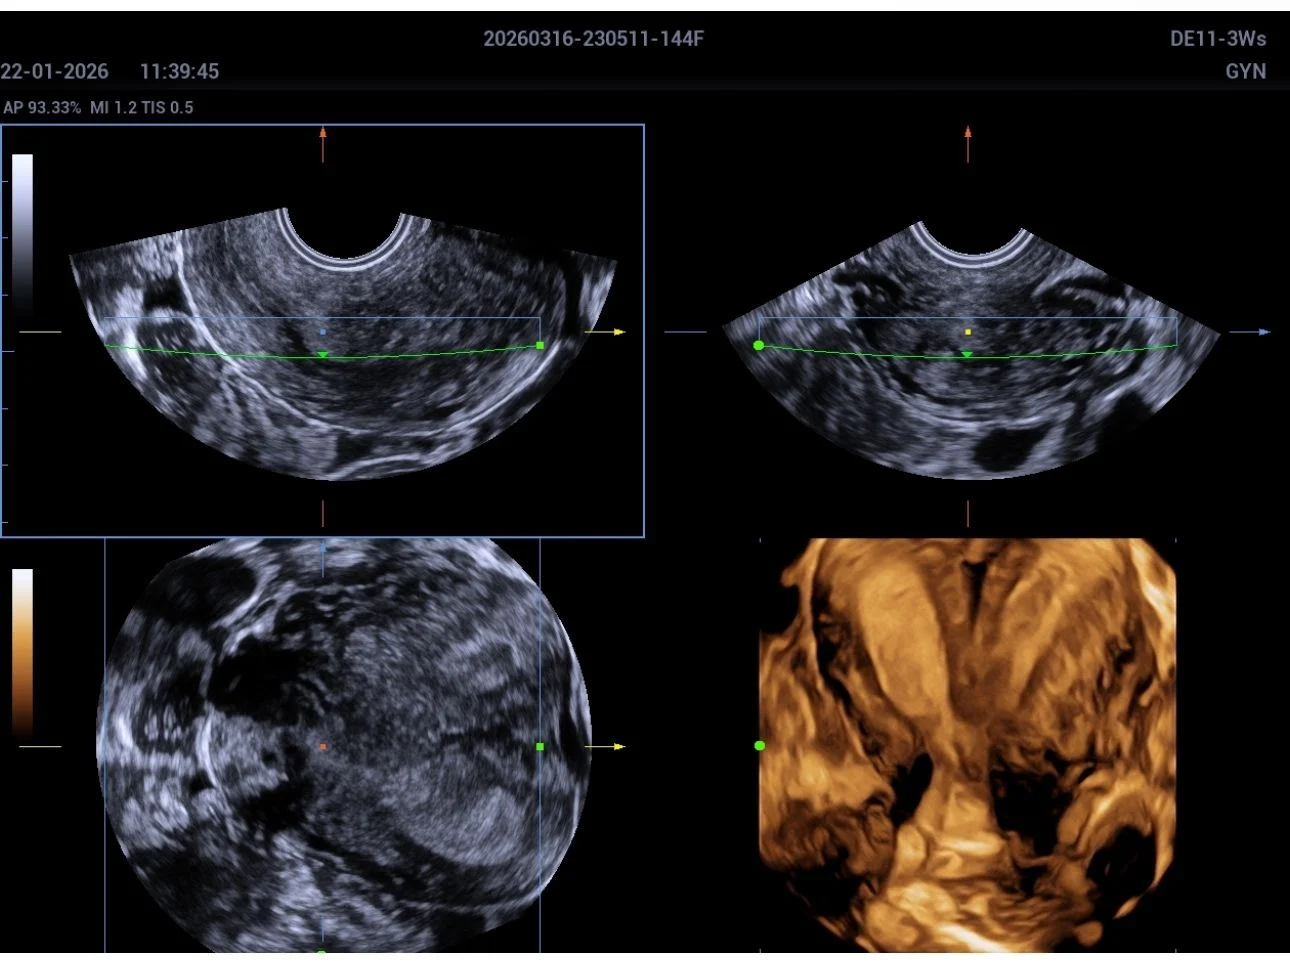

A 3D transvaginal ultrasound examination revealed a congenital uterine anomaly consistent with a bicornuate uterus with features suggestive of uterus didelphys.

Key Imaging Findings:

- Two well-defined uterine cavities with fundal indentation

- Partial to near-complete duplication of the uterine horns

- External fundal cleft supporting a bicornuate configuration

- Suspicion of duplication extending toward the cervix (differential with uterus didelphys)

Differentiating between bicornuate uterus and uterus didelphys can sometimes be challenging, even with advanced imaging.

3D transvaginal ultrasound plays a crucial role in accurately assessing the external fundal contour and cavity configuration.